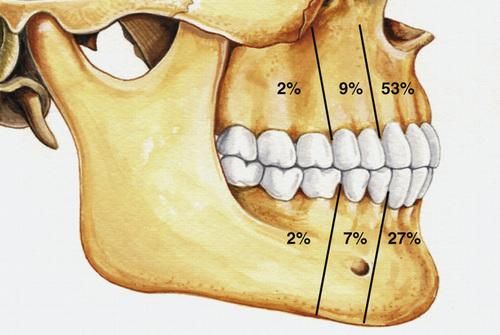

- most often involve mandibular third molars (65%)

What are the three different clinicoradiographic presentations of ameloblastoma?

- conventional solid or multicystic (80%)

- unicystic (18%)

- peripheral or extraosseous (2%)